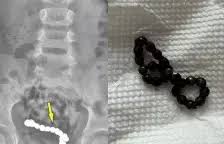

10. 엄마 배가 너무 아파요....4살 남아 뱃속에 이것 한가득

복통을 호소하던 남아의 뱃속에서 자석 뭉치가 발견됐다. 오만의 4살 소년이 1년간 지속적인 복통을 겪었다. 초기에는 단순 변비로 판단돼 관련 치료를 받았지만 증상이 호전되지 않았다. 이에 추가로 엑스레이 검사를 받은 결과, 하복부에 동글한 이물질이 여러개 붙어 있는 것을 확인했다. 현지 소아과 병원 의료진은 복강경 수술을 진행했고 소년의 뱃속에서 22개의 자석이 발견됐다. 이 자석들은 서로 붙어 팔찌처럼 보이는 상태였다. 수술 후 소년은 4일만에 퇴원했으며 3개월 뒤 추적 관찰에서도 특이 증상은 나타나지 않았다. 섭취된 이물질의 약 80%는 합병증 없이 위장관을 통과한다. 그러나 여러 개의 자석을 섭취할 경우, 장의 여러 부분에서 서로 끌어당겨 장 운동을 방해하고 벽압박괴사를 유발할 수 있는 위험이 있다. 이는 장천공, 누공 형성, 장염전, 장폐색, 복강 내 패혈증 및 사망으로 이어질 수 있다. 한편 이식증을 앓는 사람들은 보통 사람들이 상상할 수 없는 물건을 섭취한다. 손톱을 물어뜯어 삼킨다거나 머리카락, 종이 흙 등을 먹는 사례들이 많다. 특히 못, 경첩, 손톱깎이, 찬장 손잡이, 식기류 등 목구멍으로 넘기기 어려울 것 같은 물건들을 삼킨 사례들도 있다. 만약 영양학적으로 아무런 가치가 없는 물건을 1개월 이상 지속적으로 먹는다면 이식증일 수 있다. 이식증은 철분 아연 등 특정 영양분이 결핍할 때 일어난다는 보고가 있지만 대체로 정신장애 및 발달장애 등과 연관이 있을 것으로 분석된다. 이식증이 지속되면 영양 상태가 불균형해질 수 있다. 물건에 포함된 화학물질이나 세균 등으로 인해 납중독증 등 합병증이 발생할 수 있다. 따라서 건강했던 어린이에게 갑작스러운 기침, 구역질, 침 흘림, 또는 수유 거부가 나타나는 경우 주의해야 한다. 다만 아동의 경우 이식증은 여러 달 지속되다가 저절로 사라질 수 있다